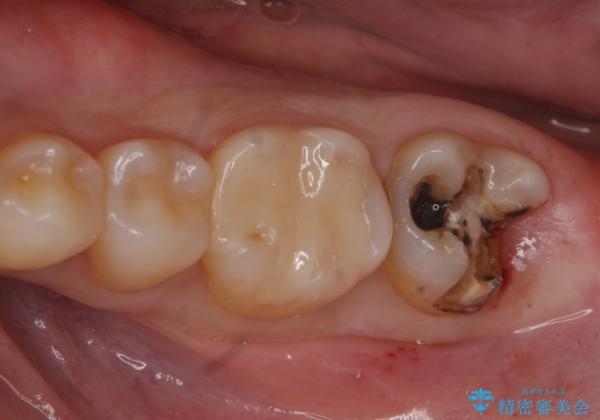

- 銀の詰め物が取れたとのことで来院。

詰め物の下には虫歯がありました。

白い物で治療して欲しいとのことで、セラミックの詰め物だと詰め物の範囲が大きく、割れてしまう可能性があるので

ジルコニアクラウン(被せもの)で治療を行いました。

銀の詰め物はかなり昔に治療されたそうです。

銀の詰め物は虫歯の再発リスクが高く、歯に痛みが出てしまうと歯の神経の治療もしないとならなくなってしまいます。

定期的なメンテナンスを行うことが大切です。